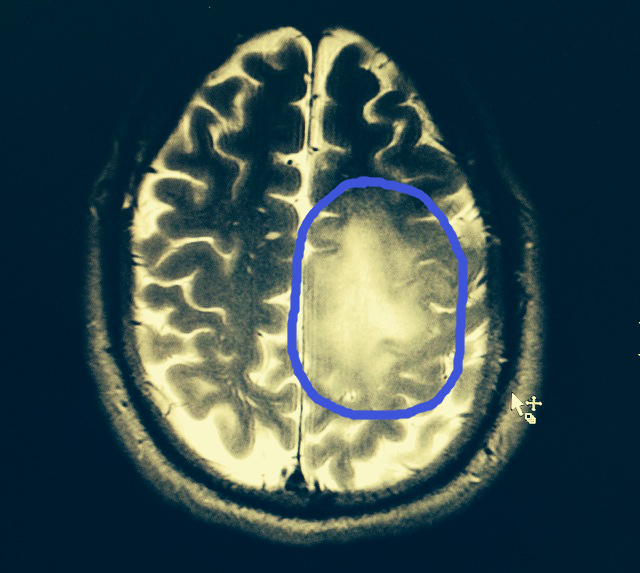

So, here is a scan of my brain and the Tumor is circled. Its bigger than first thought. On the 9th I have one more MRI w/ spectroscopy to determine the rate of growth and cell types. Then it gets really hairy.